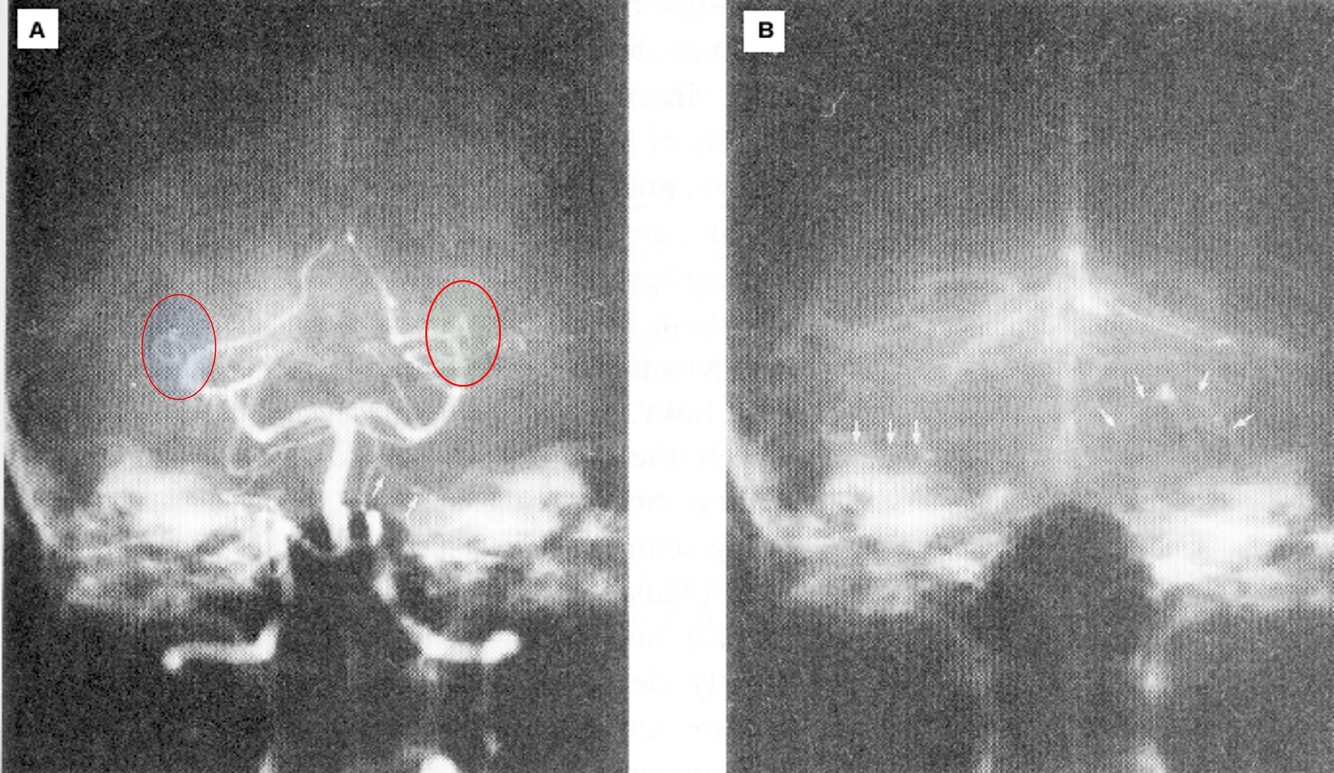

How does MRI work?

Atoms with odd protons spin -> micro atom magnetic fields

They can be aligned by external magnetic field

And excited by radio impulse at Larmor frequency to high energy status

Jumping from high to low energy status accomplished by radiation of weak signal

In MRI, different __________, different _________ -> _________ and offers better _____________________________

In MRI, Different tissue, different signals -> images and offer better resolution for soft tissues

What is occurring in this image?

High energy status returning to a low energy one accomplished with an emission of RF energy (at Larmor frequency)

Recovery to alignment and the status of losing phase (related to T1 and T2): T1: return to aliment, T2: return to random status without external MF.

In MRI, the emission is ________________________________ and provides _______________________________

The emission is picked up by the detector and provides information about the structure

How are images formed from MRI?

Release of RF is tissue (nucleus) specific, RF detected by receiving coils, Amplitude mapped by Fourier transformation, Image created by using the signal